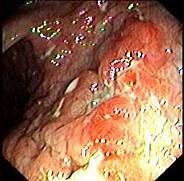

问题 女,26岁,反复右下腹疼痛4年,伴糊状腹泻,无粘液和脓血。查体:右下腹压痛,未触及包块。结肠镜检查如图,多部位活检发现炎症细胞浸润,以淋巴细胞为主,有非干酪样肉芽肿。最可能的诊断为 ( )

选项 A.溃疡性结肠炎 B.Crohn病 C.肠结核 D.慢性阑尾炎 E.细菌性痢疾

答案 B